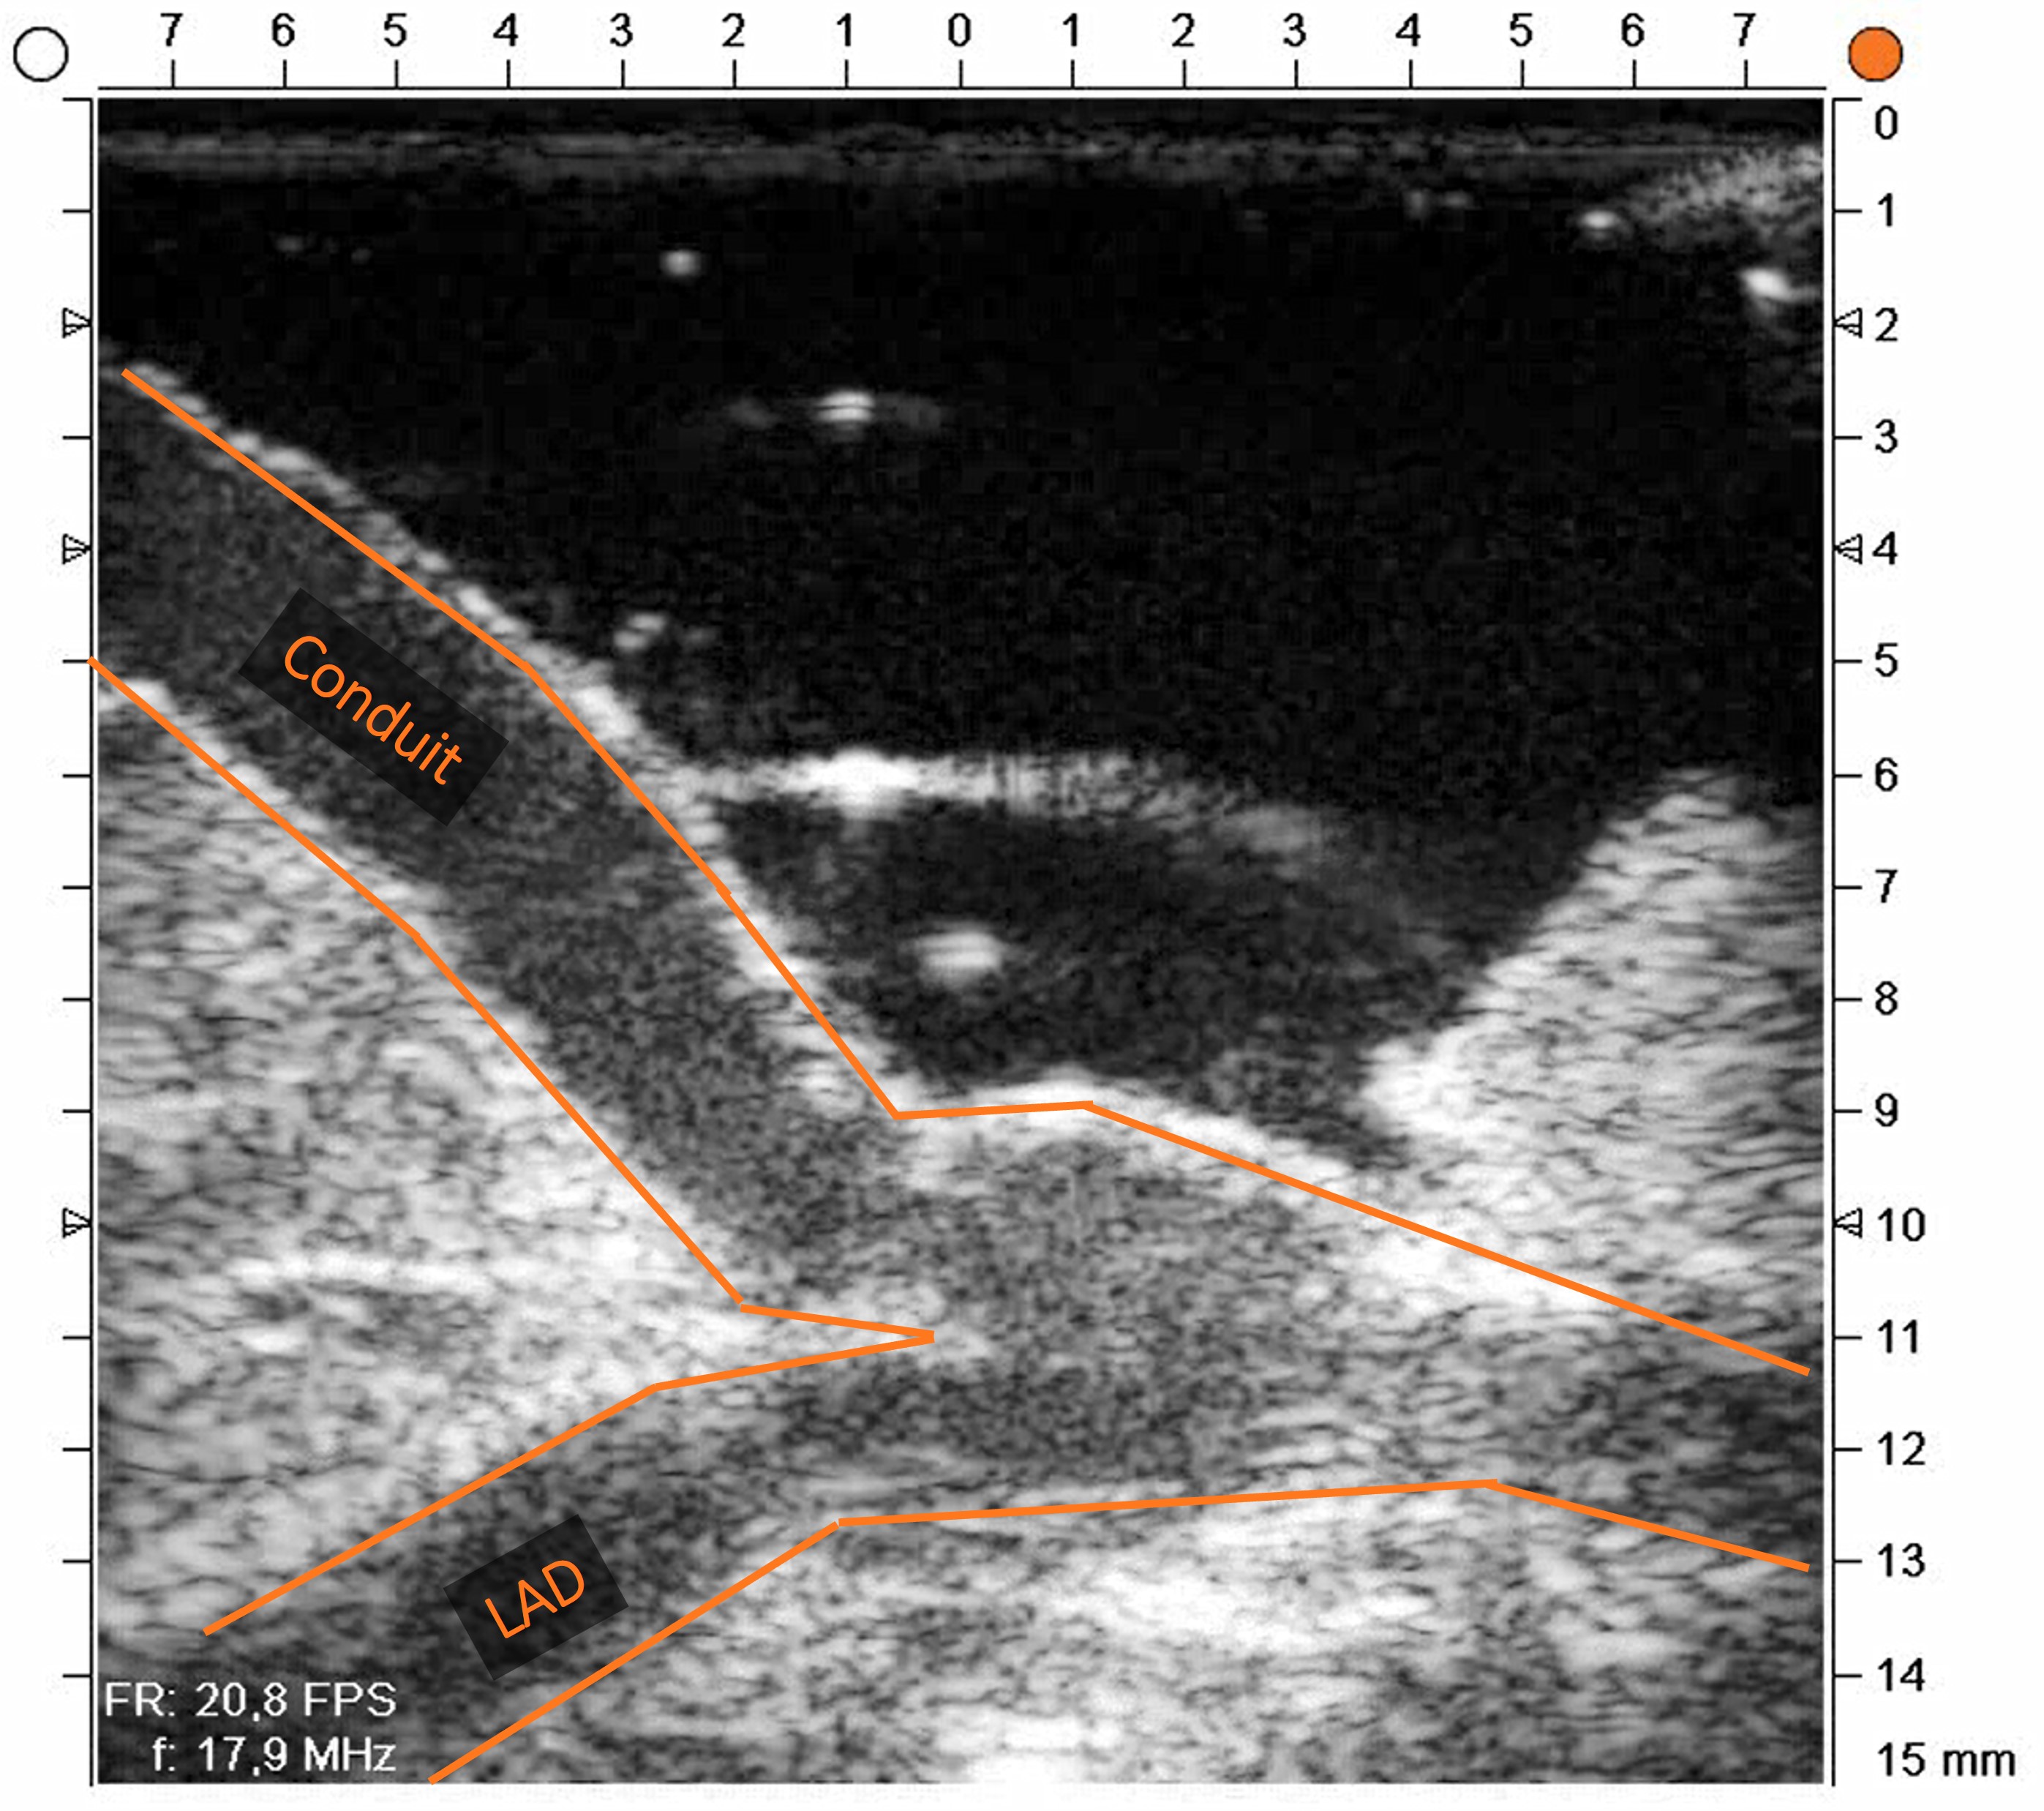

• Anastomosis confirmed patent on intraoperative imaging. TTFM assessment showed good flow and a low pulsatility index.

Conduit and LAD during CABG

Image of anastomosis confirming that it is open

The REQUEST Study 2: A multicentre, prospective study evaluating the influence of TTFM and HFUS in CABG, demonstrated that combining flow measurements with high frequency imaging improves intraoperative decision-making and supports graft quality at closure. This case is a direct illustration of that principle applied to the most technically demanding subset of targets: vessels you cannot see.